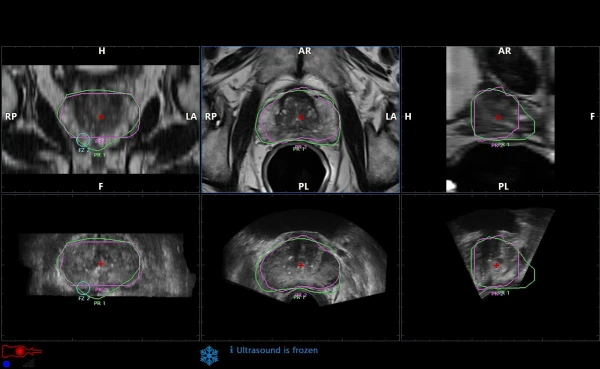

Maqsadli biopsiya uchun avtomatik ro'yxatga olish bilan prostata bezining MRI / ultratovush tasvirlarini segmentatsiyalash;